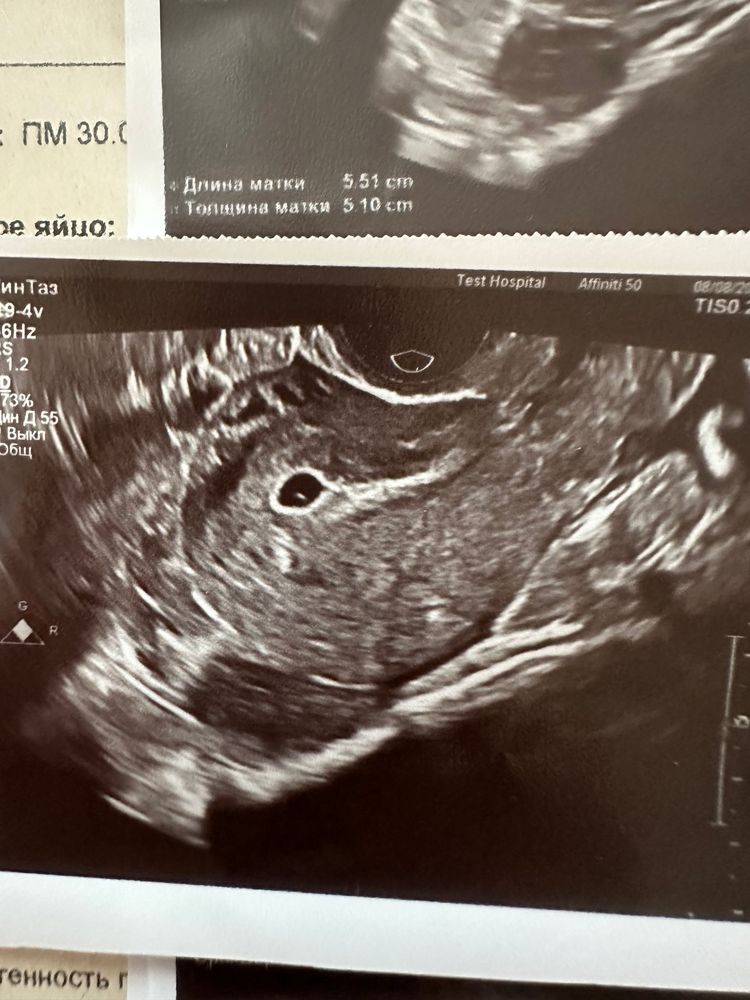

Сабрина, Изображение Изображение А вот узи сегодняшнее

10.08.2023